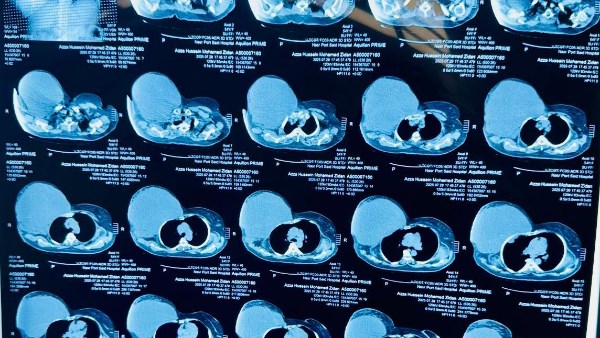

أعلنت الهيئة العامة للرعاية الصحية، برئاسة الدكتور أحمد السبكي، رئيس الهيئة والمشرف العام على مشروع التأمين الصحي الشامل، عن نجاح فريق طبي بمستشفى السلام ببورسعيد في إجراء عملية جراحية دقيقة ونادرة لسيدة خمسينية، تضمنت استئصال ورم ضخم يزن ستة كيلوجرامات من جدار الصدر الأمامي مع إعادة بنائه.

وتعود تفاصيل الحالة إلى استقبال مستشفى السلام لسيدة تبلغ من العمر 55 عامًا كانت تعاني من ورم ضخم في جدار الصدر بلغ حجمه 40 في 30 سنتيمترًا، واستمر أكثر من ثمانية أشهر بعد رحلة طويلة من المعاناة بين عدة مستشفيات دون جدوى. وبمجرد دخولها المستشفى، وضع الفريق الطبي خطة علاجية متكاملة انتهت بإجراء العملية بنجاح كامل واستئصال الورم وإعادة بناء القفص الصدري باستخدام أحدث التقنيات الطبية، واستغرقت العملية عدة ساعات بمشاركة فريق متعدد التخصصات في جراحة الأورام والجراحة العامة وجراحة التجميل والتخدير والعناية المركزة.